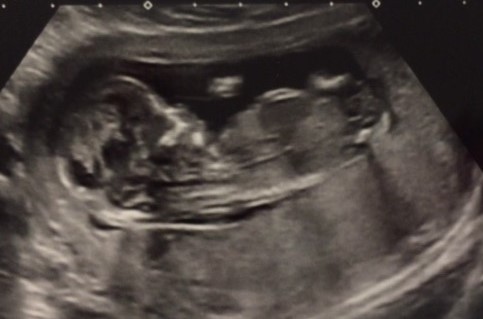

Tricky as there is a little bump above a flat line. The line makes me think girl but the bump might be a scrotal bump. I'm hesitantly girl.

Do you have any others? Not a great view of the nub. How far along are you?